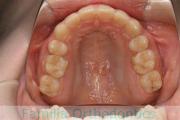

上の前歯の隙間が気になるので治したい、ということで来院されました。マウスピース型矯正装置のひとつ、インビザライン/Invisalign®(薬機法および医薬品副作用被害救済制度の対象外)を用いて治療しました。

非抜歯で1年強、12回の通院で治療が完了しました。

上顎

下顎